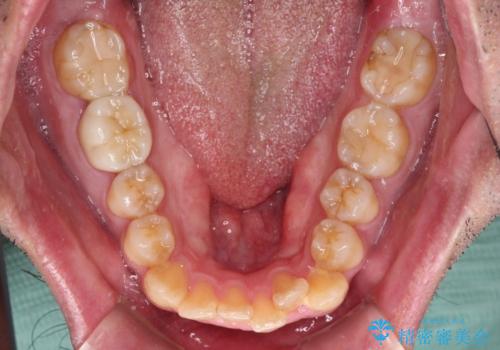

- 前歯のデコボコを治したいとのことで来院された患者様です。

できる限り楽して、短期間で治したいとのことで、ワイヤー装置にて矯正治療を行うこととしました。